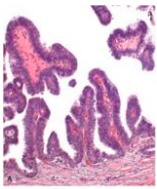

Papillary

Front

Exophytic growth pattern with fibrovascular cores supporting proliferative epithelium Cauliflower or coral shaped structures with branching fibrovascular core

Back